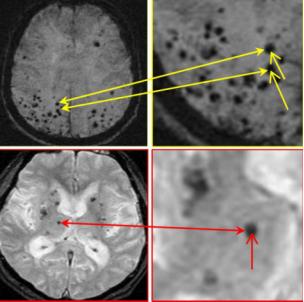

在过去的二十多年来,随着影像学技术的发展, 尤其是磁共振 T * 2 加权梯度回波成像和磁敏感加权成像) 技术的临床应用,脑微出血的研究已越来越清晰。

脑微出血是脑内微小血管病变所致的、以微小出血为主要特点的一种脑实质亚临床损害,临床上以缓慢进展的认知功能损害或者无任何临床症状为特征。

脑微出血的好发部位主要为皮层、皮层下白质、丘脑、基底节、脑干和小脑等部位。脑微出血的区域分布 以基底节/丘脑区最为多见,其次为皮质 - 皮质下区,幕下区( 包括脑干和小脑) 则少见。

解剖分布与不同的病因相关,位于大脑深部及幕下的脑微出血常为慢性高血压所致,脑叶脑微出血通常为淀粉样脑血管病所致。